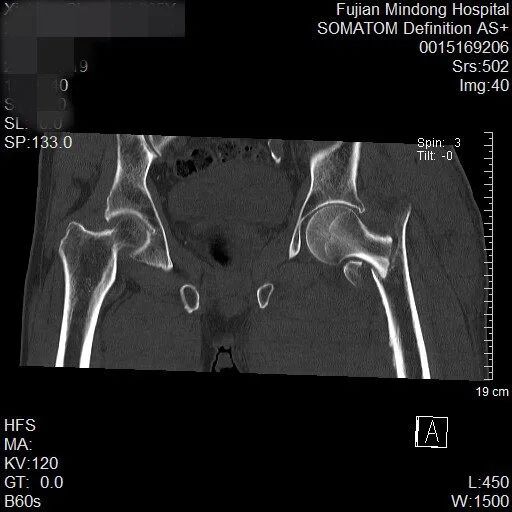

近日,霞浦县一位85岁高龄的谢大爷,因摔伤导致左髋部剧痛、无法活动,于伤后第二天前往宁德市闽东医院就诊,被确诊为“左侧股骨粗隆间骨折”。创伤骨科何晓宇主任医师与张中宁副主任医师团队,为其实施了“左侧股骨粗隆间骨折闭合复位PFNA内固定术”。整台手术耗时约一小时,术中出血量仅约20毫升,展现了微创手术的优势。令人欣喜的是,术后第一天患者便能自行坐起,第二天即可站立,第三天已在助行器辅助下开始行走,恢复迅速。

术前